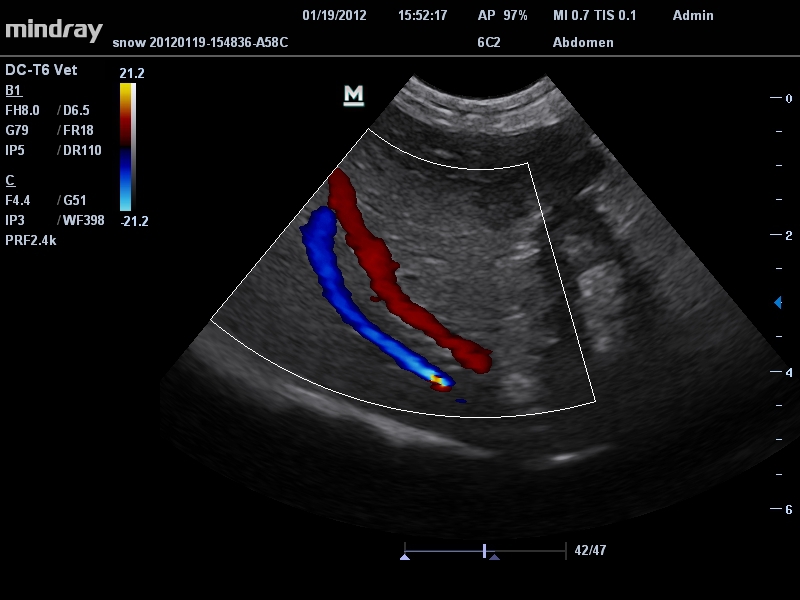

Цветовой допплер:

Да

Ветеринария:

• Режимы сканирования: B/M/CFM/PDI/Направленный PDI/PW, HPRF, Тканевая гармоника, М- и цветной М-режим.

• Микроконвексный датчик Mindray 6C2